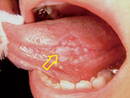

白板症は、舌に白いできものができる原因の一つとして挙げられます。この病気は、舌や口腔内に白い斑点やできものが現れる状態で、悪化するとがんになるリスクが高くなります。ここでは、白板症の治療法について詳しく説明します。

白板症の治療法には、局所的に薬物を使う方法があります。例えば、抗炎症薬や抗菌薬を塗布することで、症状を軽減することができます。これにより、白いできものが縮小したり、改善することがあります。

白板症が進行しており、薬物治療では効果が見込めない場合、手術による治療が選択されることもあります。手術で白板症を取り除くことで、がんのリスクを減らすことができます。